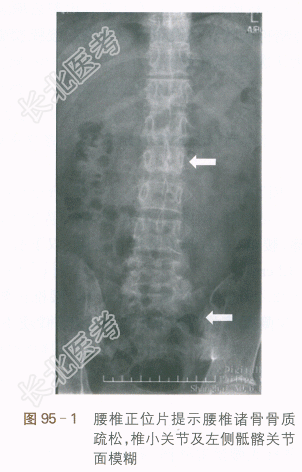

(2)腰椎正侧位X线片:腰椎诸骨骨质疏松,椎小关节及左侧骶髂关节面模糊。如图95-1、图95-2所示。